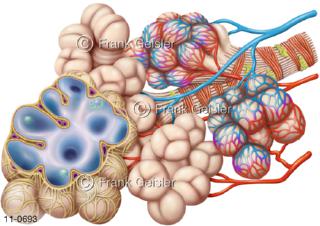

11-0693 Lungenläppchen Lobulus mit Lungenbläschen Alveolen und Blutkapillare